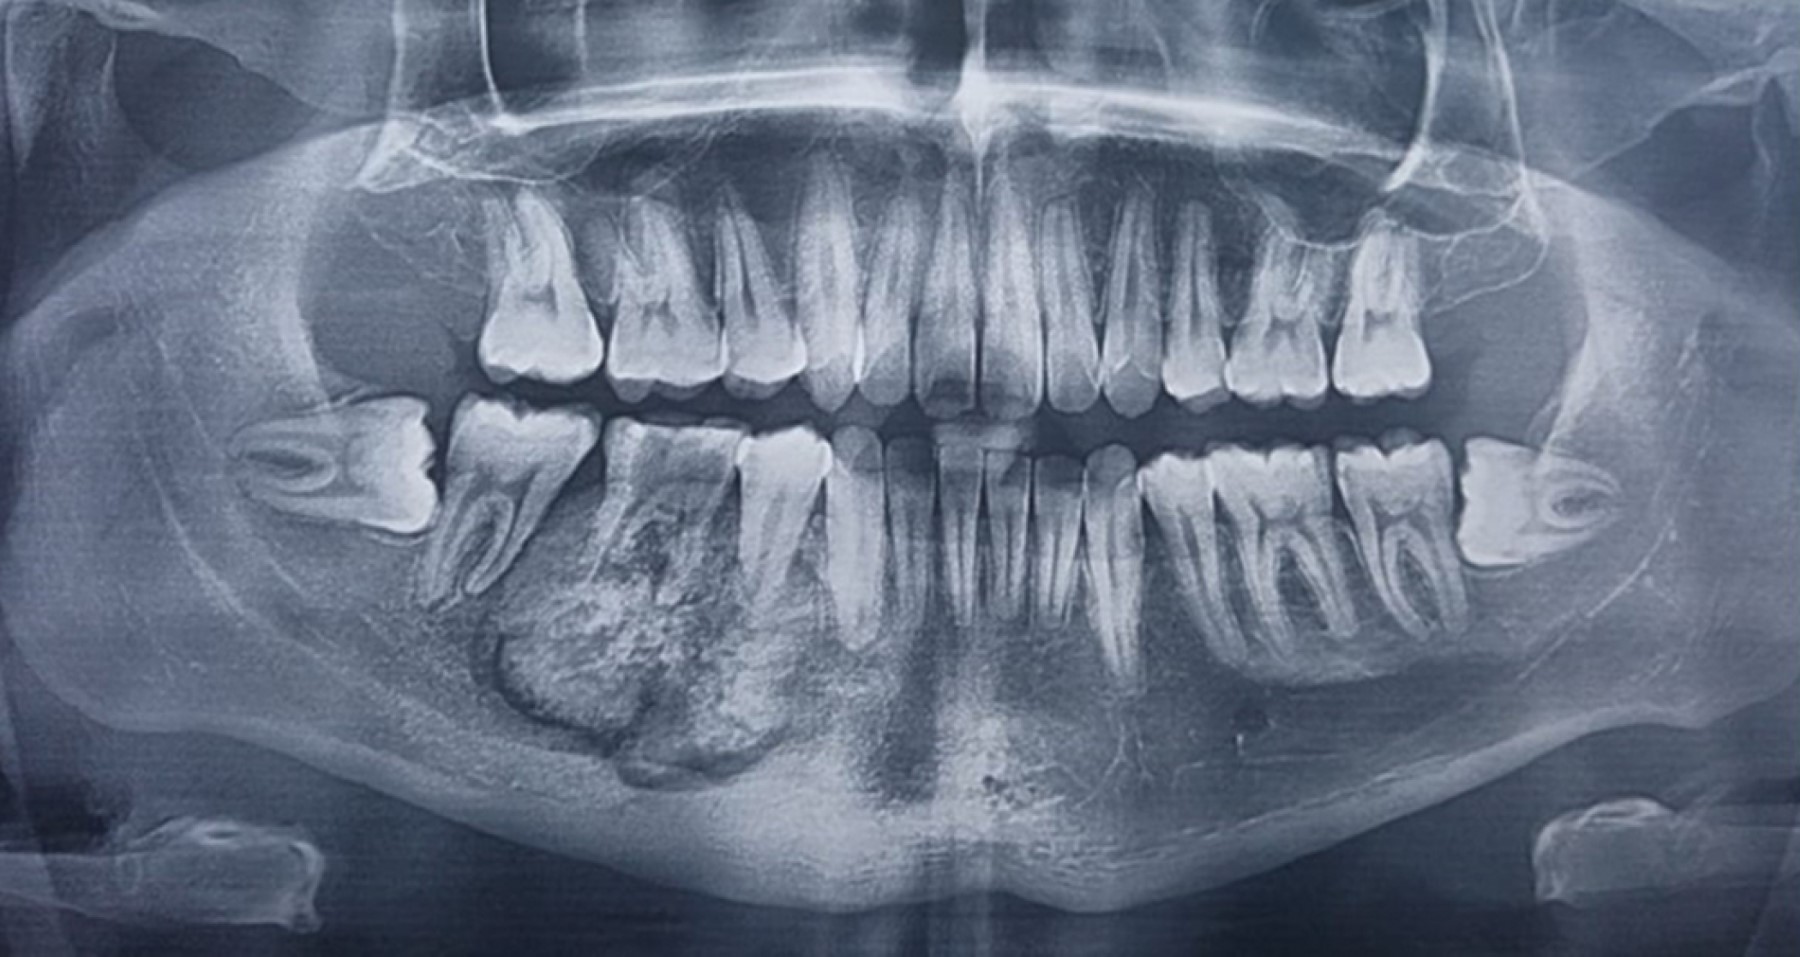

Cementoblastoma - Wikipedia Apical Radiopacities - Radiodontics Cementoblastoma: Features, Diagnosis, and Treatment Cementoblastoma. Classic appearance of a sclerotic tumor fused ... ❇ Benign Cementoblastoma Radiology: ▶ Location: → 78% in ... Cementoblastoma